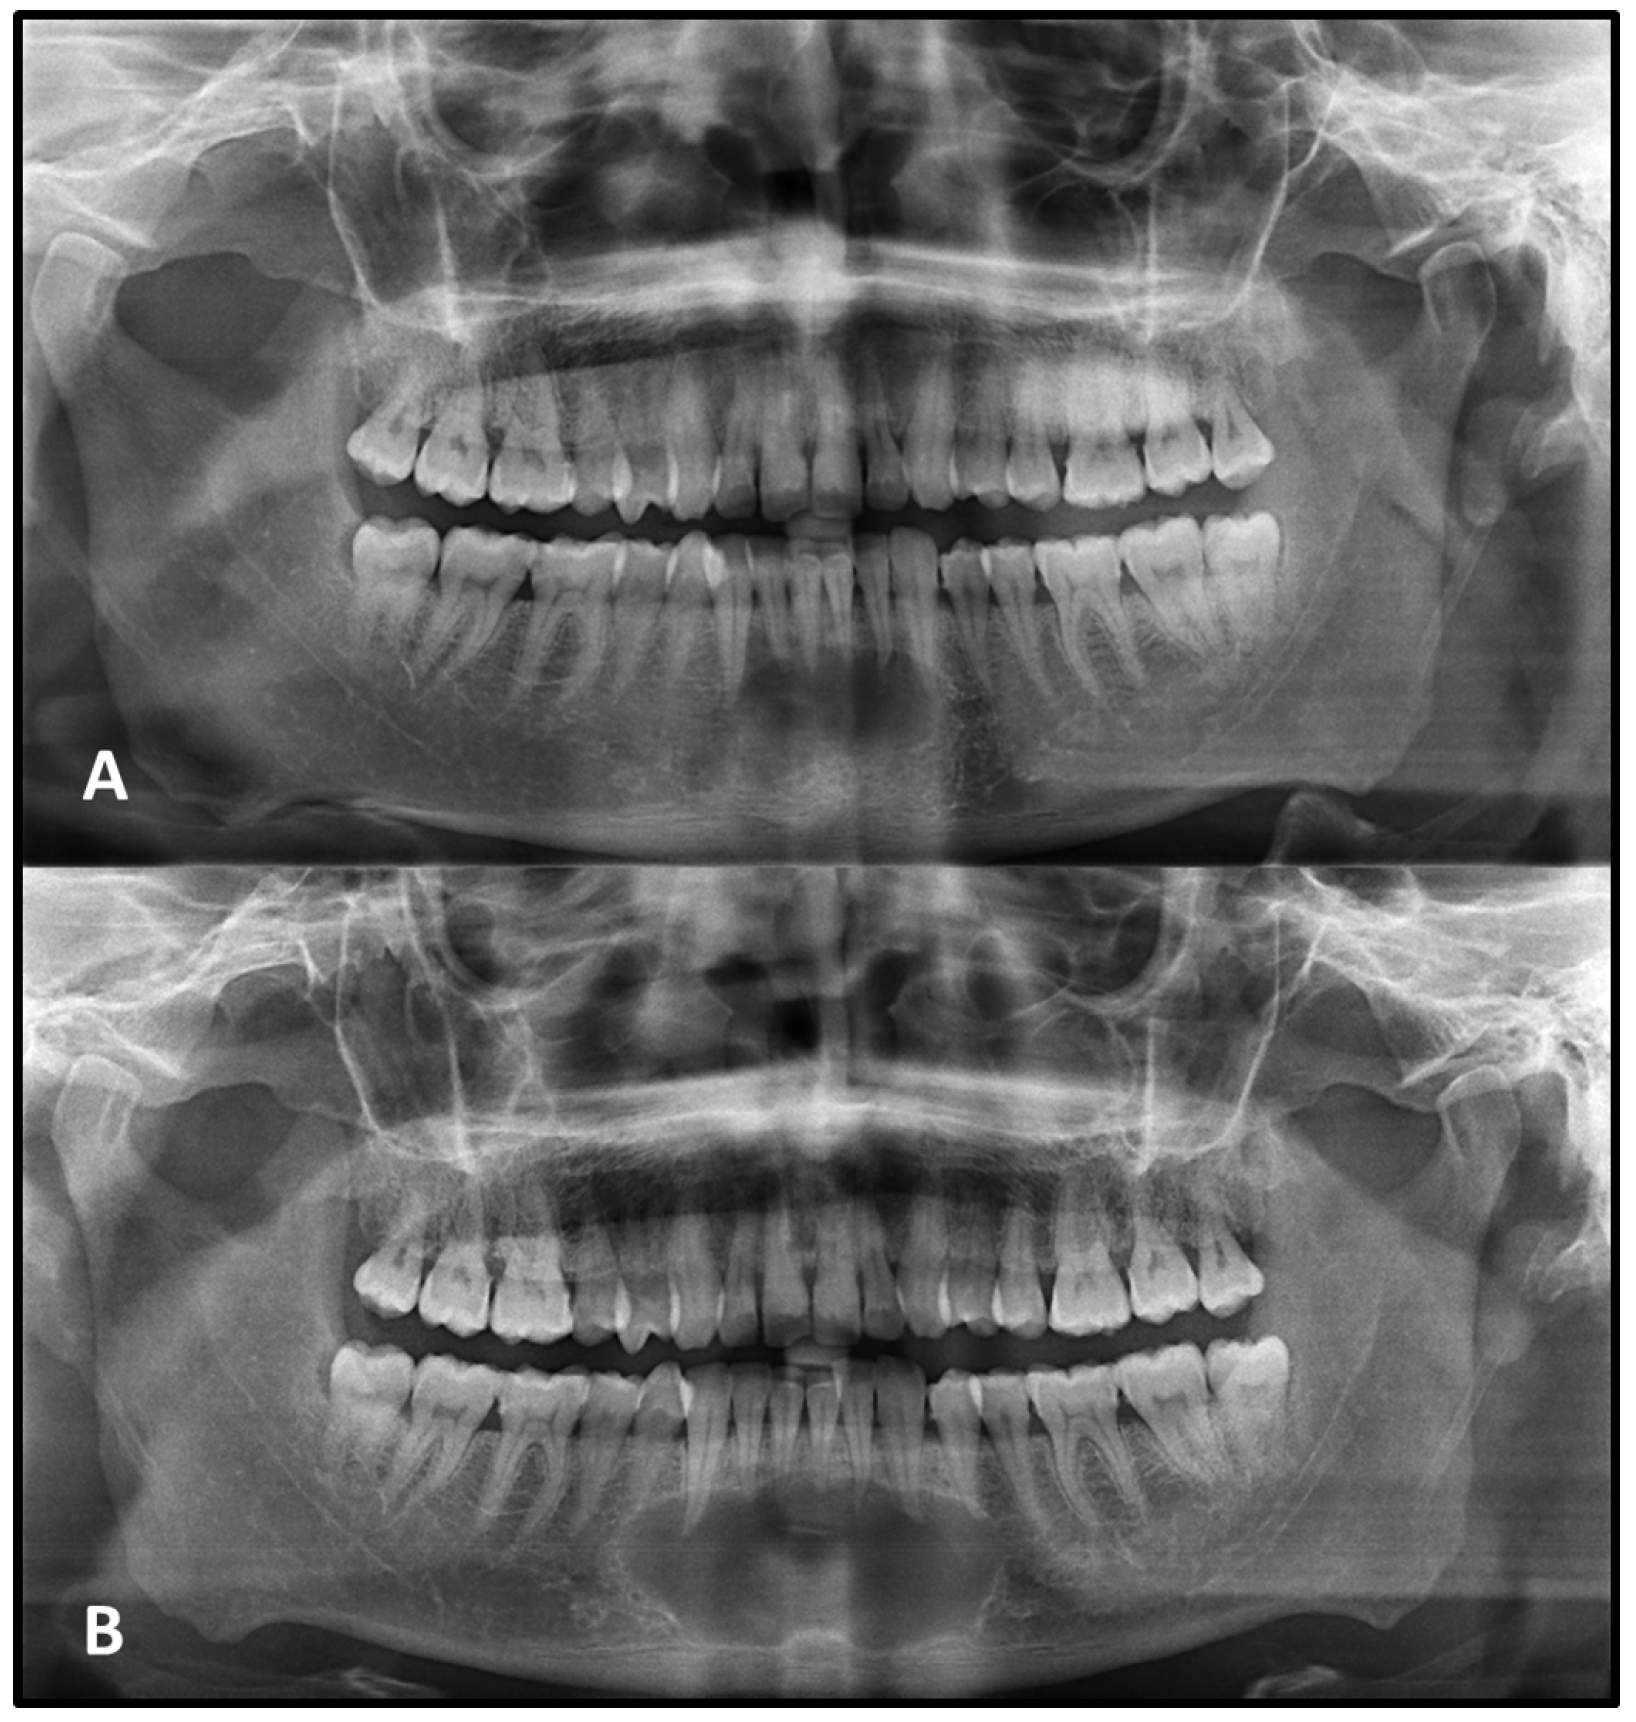

Tooth root resorption associated with the lesion was identified in 9 cases on the initial PAN. Among these, resorption remained stable in 7 cases, while 1 case showed progression, and another case exhibited involvement of additional roots at follow-up. In the second image, root resorption was newly detected in 8 additional cases that had shown no evidence of resorption initially (

Figure 4).

Cysts may cause tooth displacement and root resorption when they reach large sizes. The roots of teeth may be resorbed by either benign or malignant lesions, but root resorption is more commonly associated with benign processes [

7]. It is often associated with prolonged pressure from adjacent expanding lesions and may serve as an important radiographic indicator of lesion behavior [

7,

21,

22,

23]. In the present study, a limited number of non-surgically managed lesions exhibited root resorption that was absent or minimal on the initial PAN but became apparent or progressed in the subsequent image. However, the interpretation of root resorption on PANs is limited by their two-dimensional nature and subtle changes may therefore be underestimated compared with CBCT. Displacement of teeth is also seen more commonly with slower-growing, space-occupying lesions. A benign lesion exerts pressure on neighboring structures, resulting in the displacement of teeth or bony cortices [

5]. In the present study, tooth displacement was observed even less frequently, generally in cases with significant lesion enlargement. This change may be attributed to the gradual thinning and remodeling of the adjacent bone, reducing mechanical resistance and facilitating positional shifts in neighboring teeth.